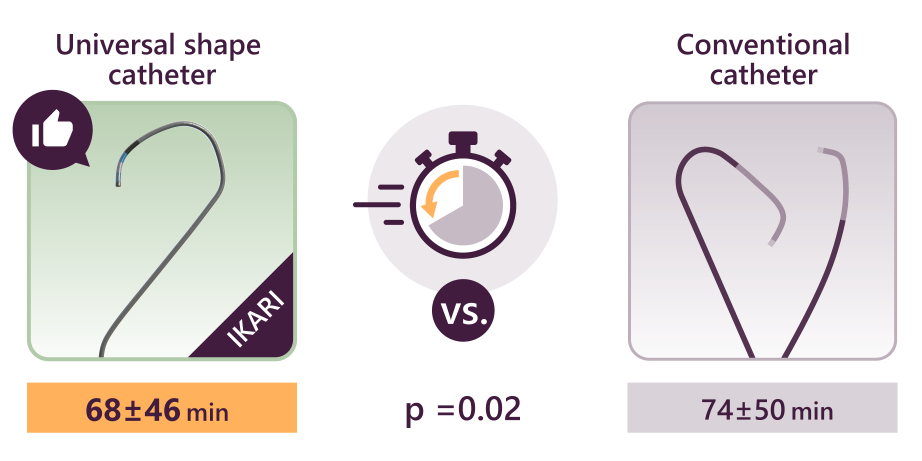

- One approach is to use a guiding catheter to establish a stable position. Using an active support catheter like Ikari left makes this easier to achieve. In fact, Ikari left not only enhances back-up support, but also contributes to reduced time in STEMI, making it a very versatile shape.